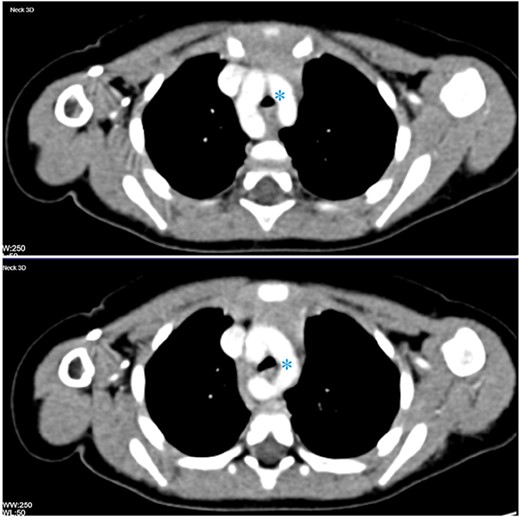

Post-operatively, a contrast-enhanced computed tomography (CT) of the neck and chest was obtained and a vascular ring, consisting of a double aortic arch, was found compressing and narrowing the trachea (Fig. 2).

Contrast-enhanced CT of the chest in two consecutive axial cuts showing duplication of the aortic arch encircling the thoracic trachea and oesophagus (asterisk).